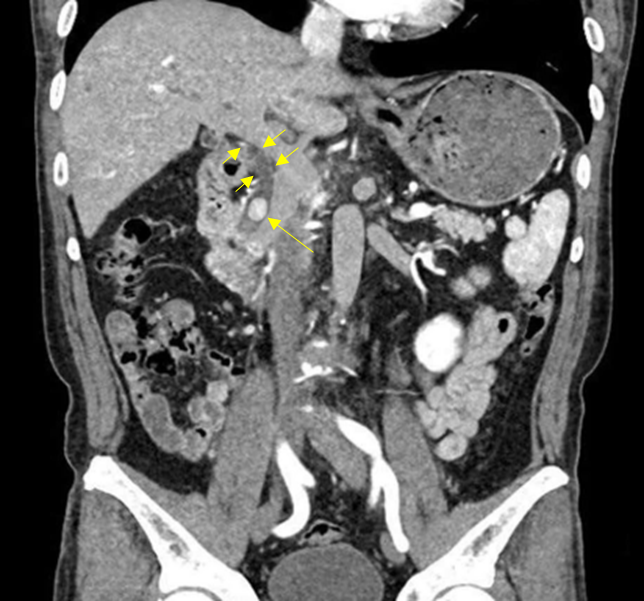

Img | CT: CBD stone with upstream biliary dilatation |

Obstructive jaundice가 동반된 septic shock이 있으며 CT상 CBD stone 및 upstream CBD dilatation이 확인되므로 acute cholangitis로 진단한다.

• CT상 CBD stone이 확인되고, 그보다 upstream하게 bile duct dilatation이 저명하므로 acute cholangitis에 의한 septic shock으로 진단한다.